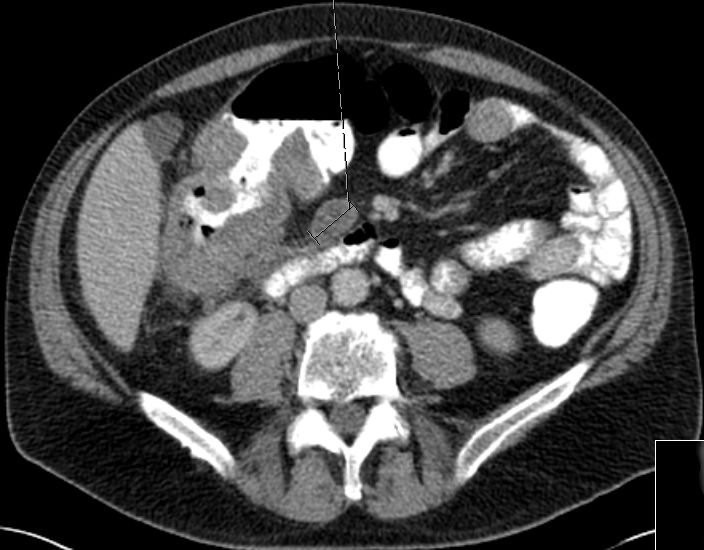

| Beispiele bildgebender Diagnostik von primären Colonkarzinomen | Zökum |

Colon ascendens |

Colon descendens | |